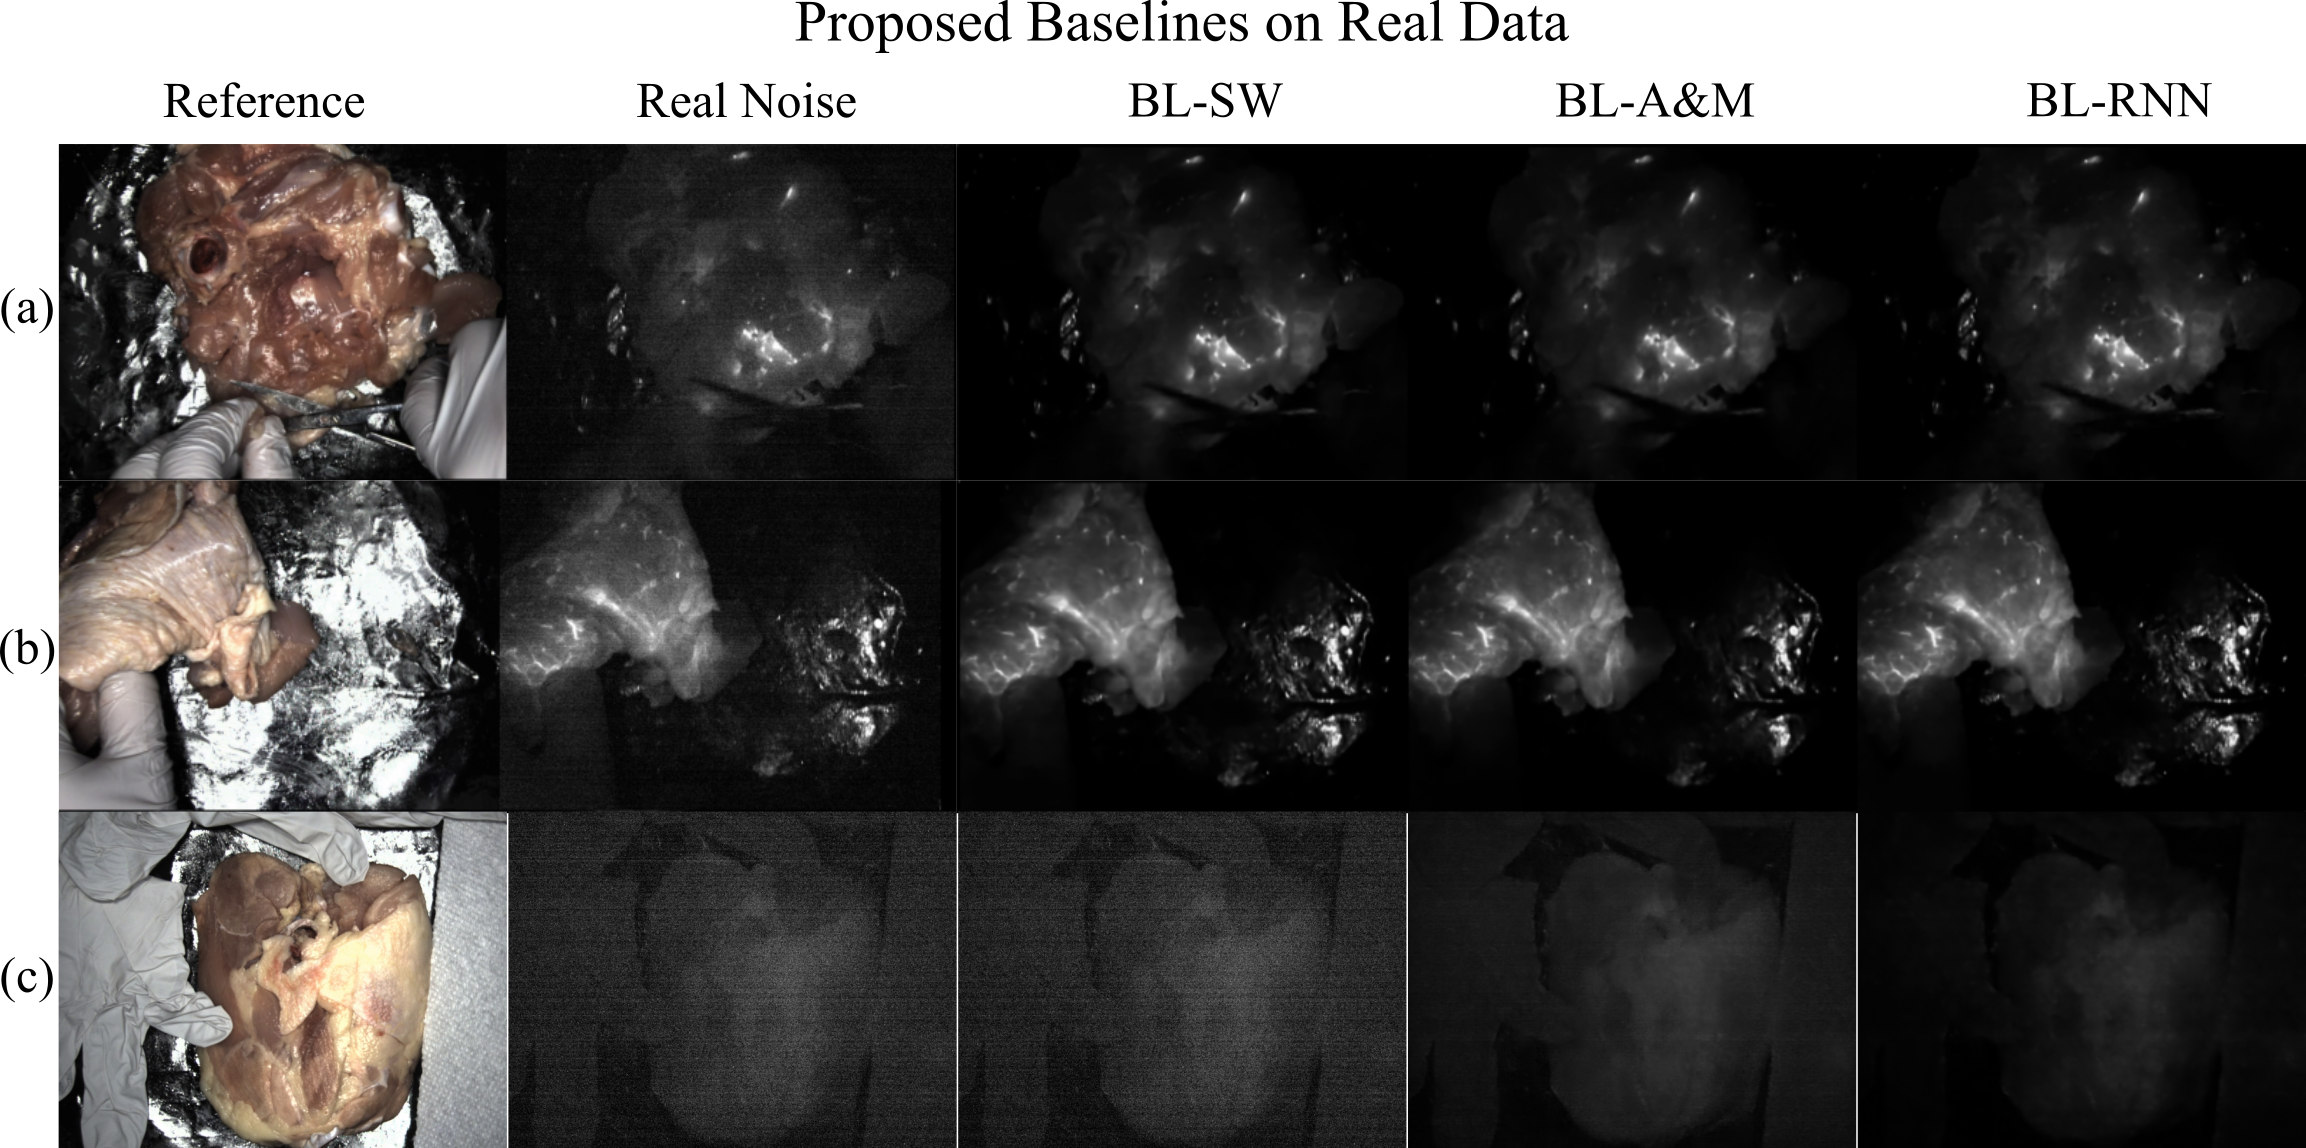

Figure 10: OL-2024 Results: This figure shows the results of our baseline models (a-b) on 2 scenes from OL-Real. Notice how the hands in (a-b) are correctly removed by our baselines. (c) shows a scene with no fluorescent agent injected, BL-RNN is able to correctly remove most of the LLL in this scenario.

V-E Real Test Data

We test our models on OL-Real; however, because we lack ground truth we can not compute metrics on the results. Example result images are shown in Fig. 10(a-b). We find that all our baseline models are able to perform reasonably well on OL-Real. See supplement for video results.

In another test example we input real noisy data that contains no added fluorescence; the results are shown in Fig 10(c). For this test, we want a model that correctly finds that no fluorescence is present and outputs a image of all zeros. Note this training example is outside of the training regime of the models so unsurprisingly many of them struggle with this task. Surprisingly, BL-RNN is able to generalize and properly remove most of the LLL present in this image and is the only model that correctly removes the entire LLL coming from the gloves and paper towel on the sides of this scene.